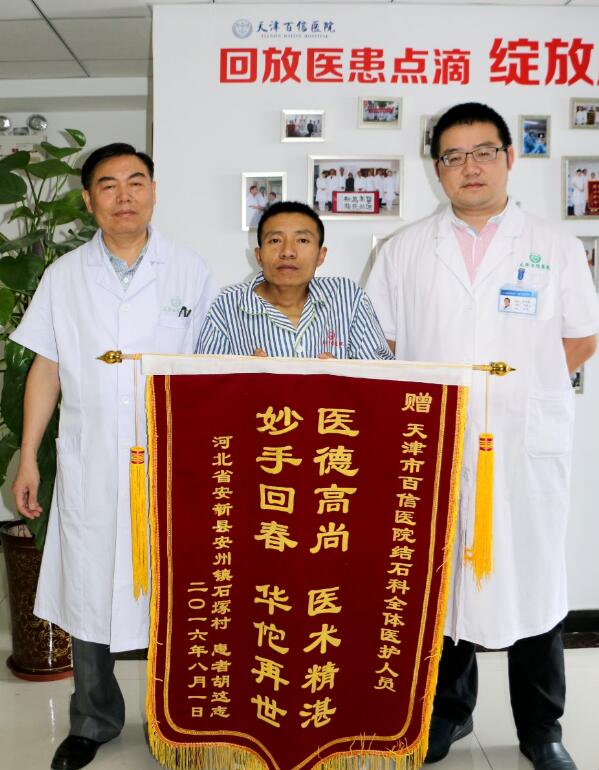

手术时间定于6月27日,经过严谨细致的术前准备,由丁德刚主任为患者进行钬激光碎石清石术的治疗。考虑到患者身体情况特殊的情况,麻醉师采用呼吸管来人工控制患者呼吸,并用药物控制心率,并且医生还人工造截石位来帮助患者保持术中平衡。丁主任凭借多年的手术经验,采用输尿管镜配合钬激光,一一清除患者输尿管内的结石,在经过两个小时的辛苦努力后,手术终于圆满的完成了。当胡先生醒来听到“手术很”的消息后,喜极而泣,不停地说:“我都没敢想能再好起来,多亏了你们,多亏了你们啊!”

手术后,住院部医护人员对胡先生进行了精心的护理。由于胡先生家住河北省,来回非常不方便,而且自从胡先生患病之后,他的妻子就担起了家庭的重担,家里的农活和上学的孩子都需要胡先生的妻子去照顾,所以她无法陪伴在胡先生身边。相对于亲朋好友经常探望的病友,胡先生的病房里往往显得格外的冷清。所以为了不让胡先生感到太孤单,偶尔发现胡先生身边少点什么,医护人员都会自掏腰包主动为他添置,丁主任还会时常跑到病房去查看胡先生的身体状况,有空的时候就会和他聊聊天,叮嘱他一些日常生活中需要注意的事项。在这样的细心照料下,胡先生的身体很快得到的康复,术后第五天,就已经可以出院了。出院前的胡先生拉着每位医护人员的手表示感谢,激动地流下了热泪!

8月2日是胡先生到医院进行术后拔管的日子,鉴于胡先生的家庭生活状况,院方决定免除拔管手术的所有费用,为胡先生免费进行后续手术,并为胡先生买好了回程的火车票,让胡先生能够加安心的回家。胡先生此时没有说一句话,但是那颤抖的双手和眼中的泪光足以表达出他内心的感激之情……

他表示想找到媒体,把他在天津百信医院经历的这段日子报道出去,让别人能看到天津百信医院是一个真真正正的“待患者如家人,为患者除病痛”的好医院,让有着跟他一样疾病的患者都能到这里来,有效的解除自己的病痛,让所有病人远离病痛,让所有家庭加美满!